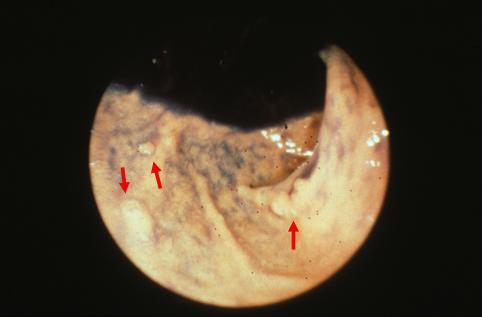

疾患(病理主体)の分類腫瘍様病変/異所性粘膜

部位(臓器別)十二指腸/球部

検査方法内視鏡

病変の最大径(ミリ)1〜9